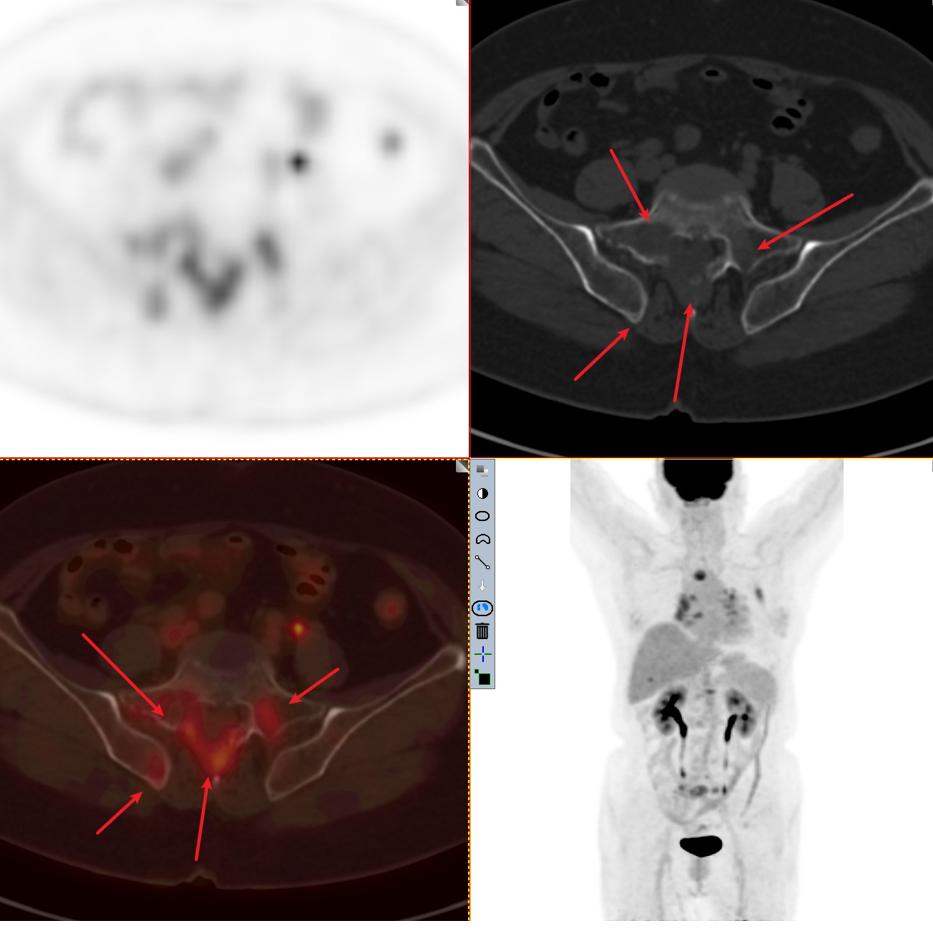

图4-5分别提示:胸骨、腰椎、骶骨及右侧髂骨骨转移。

因此该患者的肿瘤分期与第一位患者截然不同,同样病灶都在3cm以内,该患者属于T1cN3M1c 属于ⅣB期 最晚一期。这例患者当然不能手术了,只有寄希望于基因检测,如果有匹配的靶向药物,结合全身化疗或者免疫治疗,有一部分人还是有不错的效果。